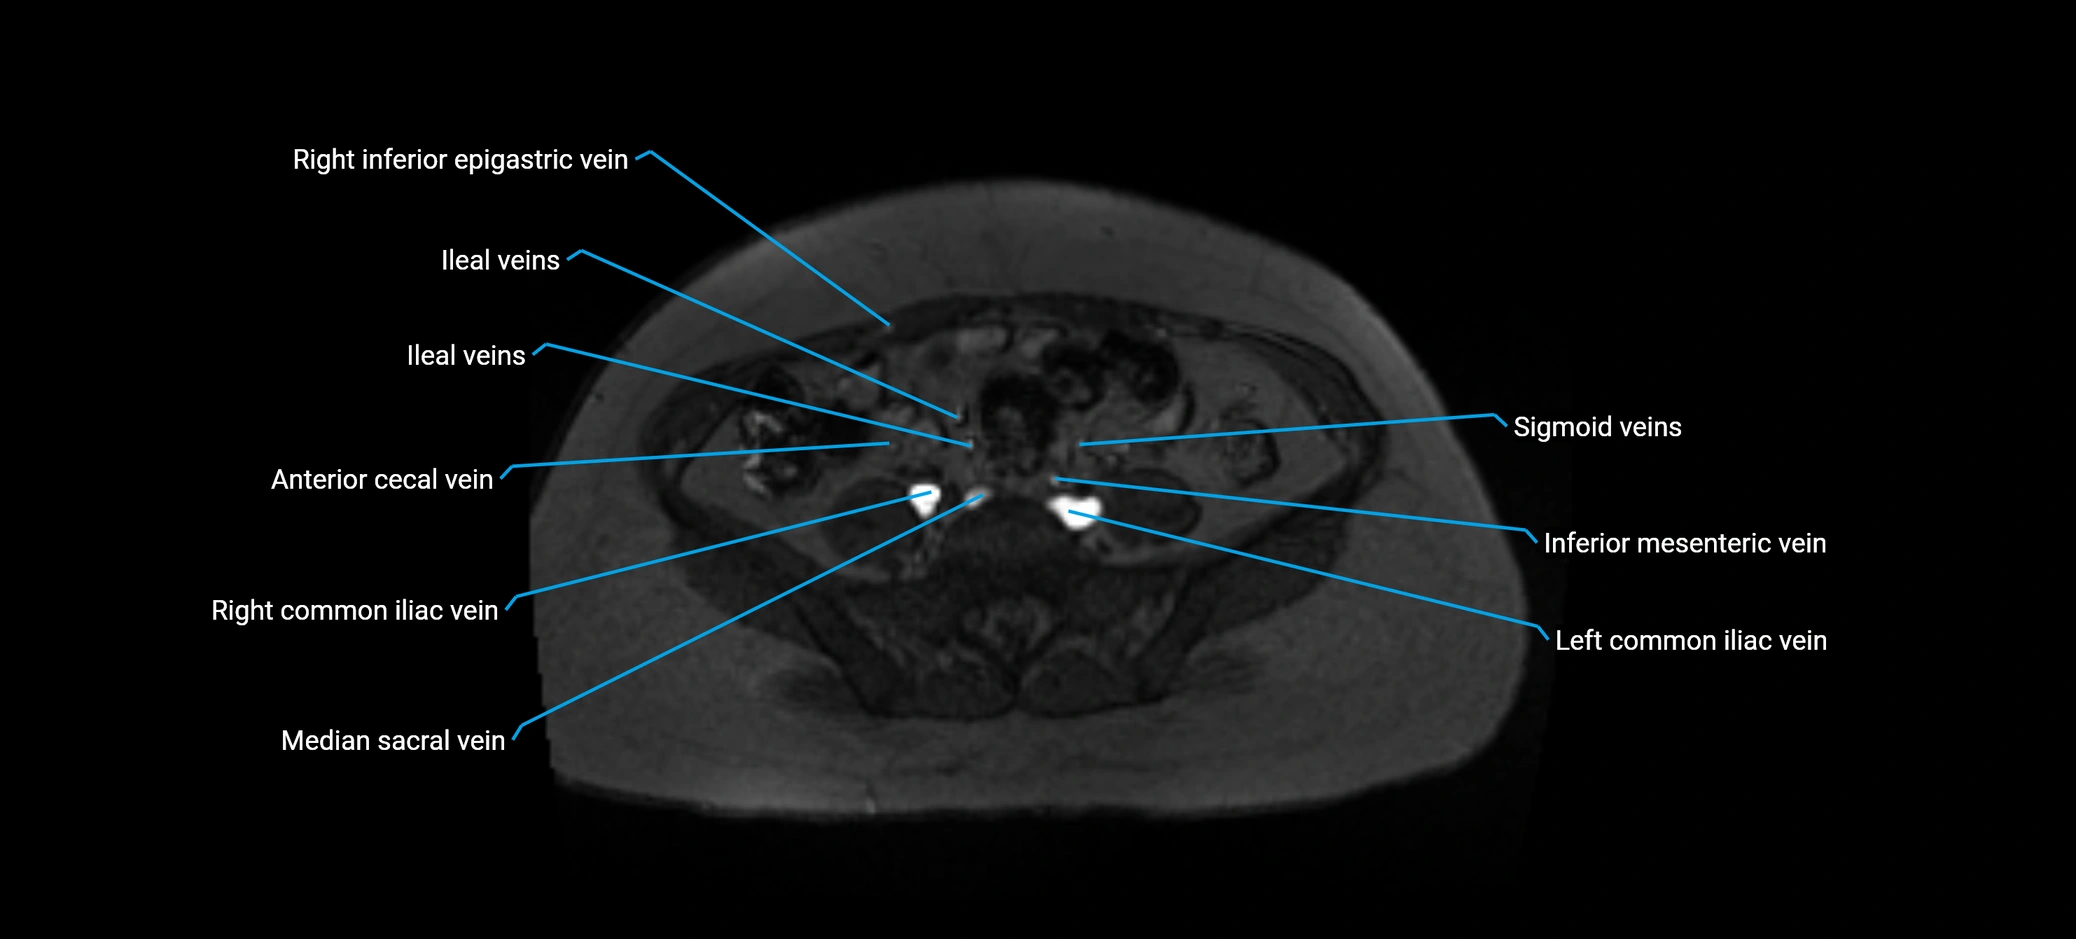

MRI image

image